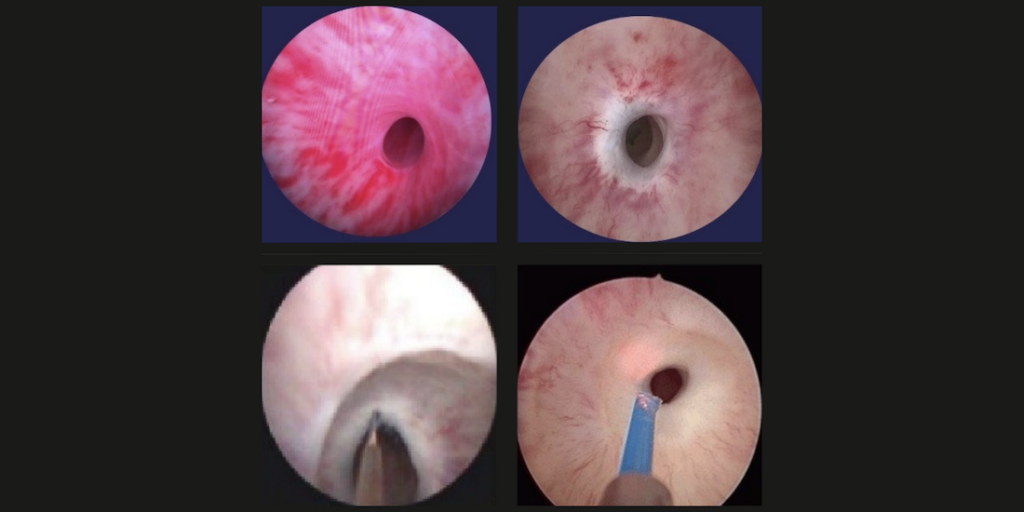

La uretromeatotomía es un procedimiento quirúrgico ambulatorio que se realiza para ampliar el meato uretral y el segmento distal de la uretra cuando existe una estrechez que dificulta la salida normal de la orina 🚻

Es una intervención frecuente en casos de estenosis del meato o estenosis uretral distal.

🏥 ¿Cómo se realiza?

El objetivo es eliminar la obstrucción y restablecer un flujo urinario adecuado.

- 1902057: Uretrotomía interna endoscópica.

- 1902062: Uretrocistoscopía.